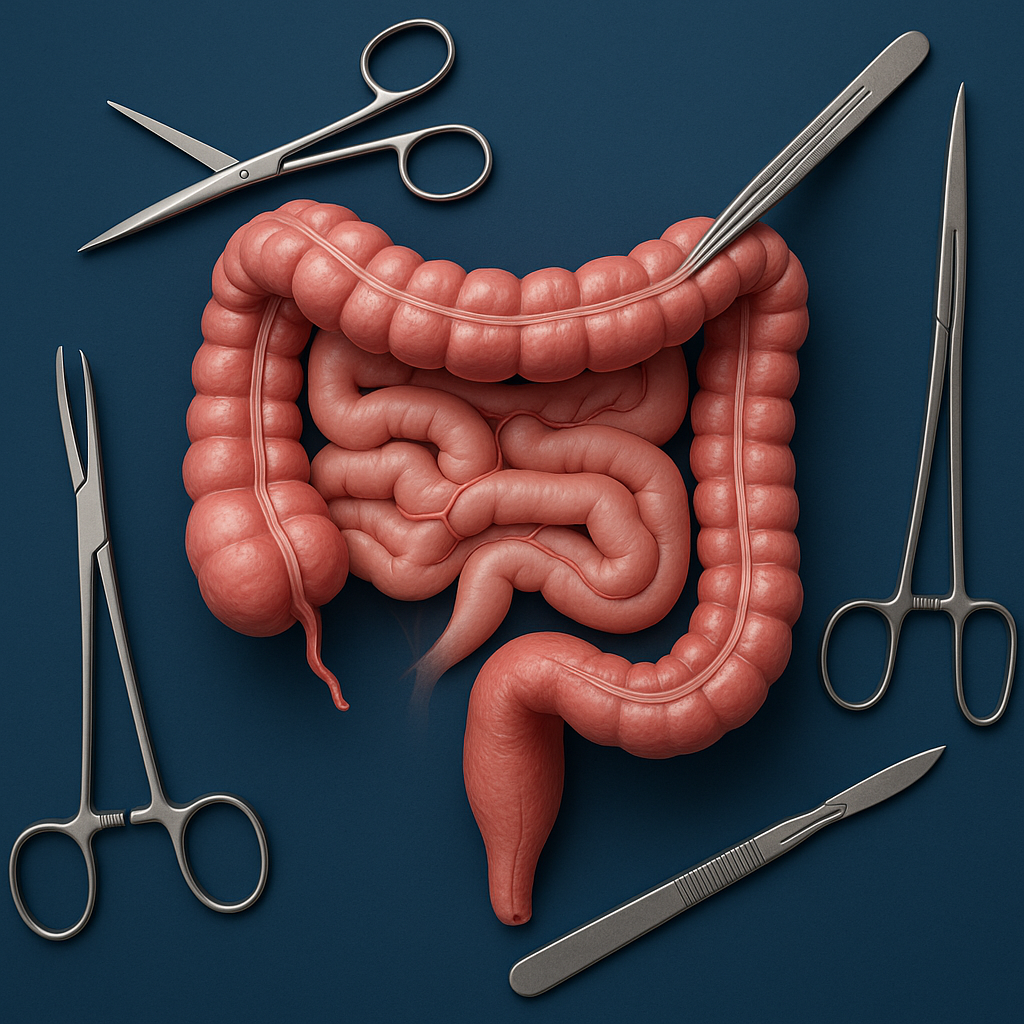

General & Laparoscopic Surgery